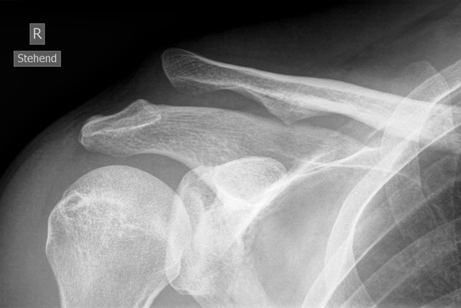

Ac Gelenk Verletzung Schulterzentrum Saar Dr Gross

Wenn es stationär unter Vollnarkose gemacht wird was aber selten ist 2-3 Tage. 15 cm aus dem Schultergelenk herausstand ohne die Haut zu durchstossen. Schultergelenkssprengung tossy 3 oder luxation A C links.